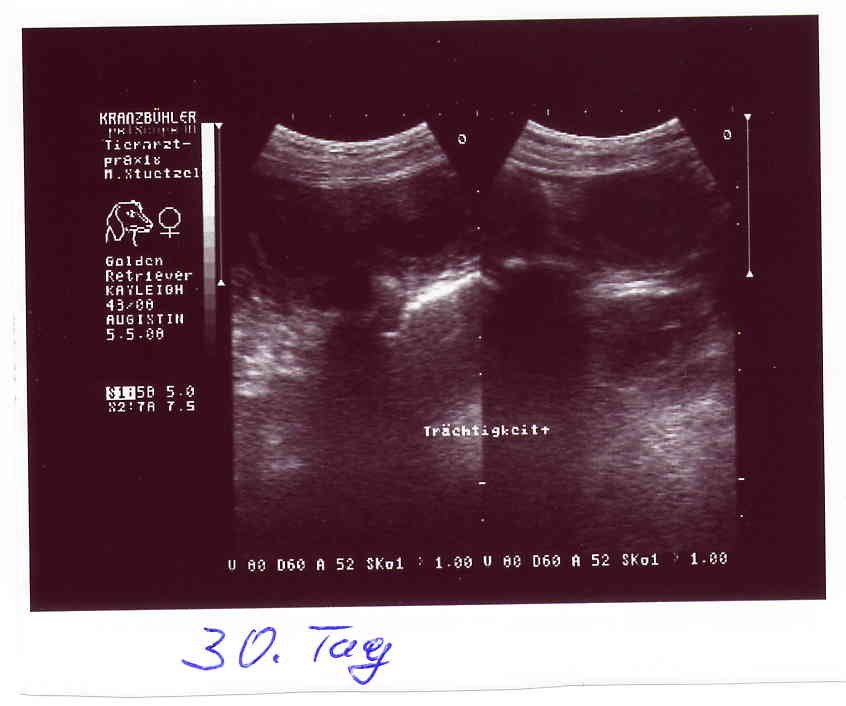

4 Wochen, o7.o5.o8 ja ich bin trächtig Verstehe einer die Zweibeiner |

Das Beweisfoto

Bin ich's oder bin ich's nicht??? Macht schwanger schön??? |